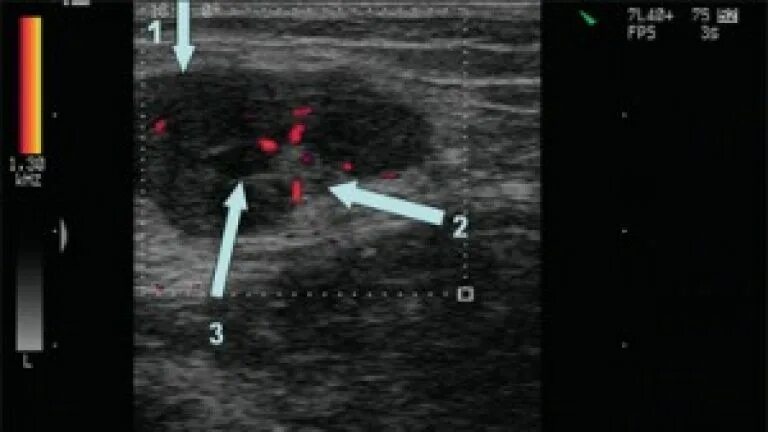

Лимфоузлы гиперплазированы